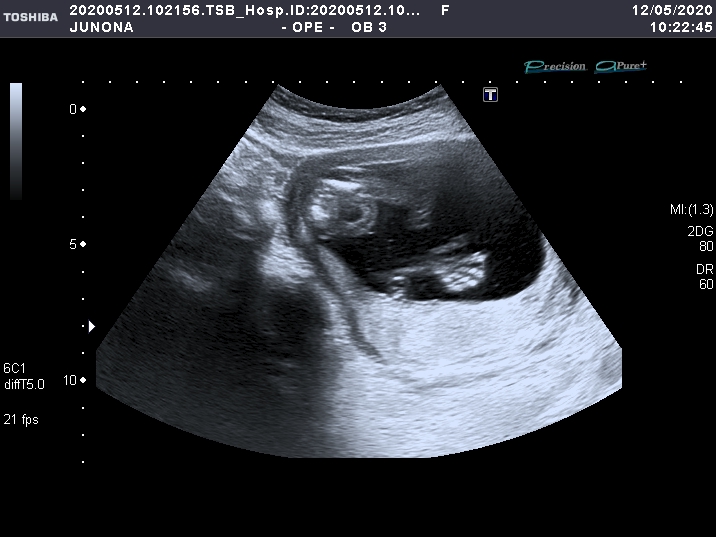

УЗИ, КТГ, доплерНу что, девочки) сходила сегодня на УЗИ) кружок уже закрасила🔘. У нас будет МАЛЬЧИК) Я плакала. Мужу и родным буду сообщать в интересной форме-чуть позже)

Вот он наш мальчишка 👇